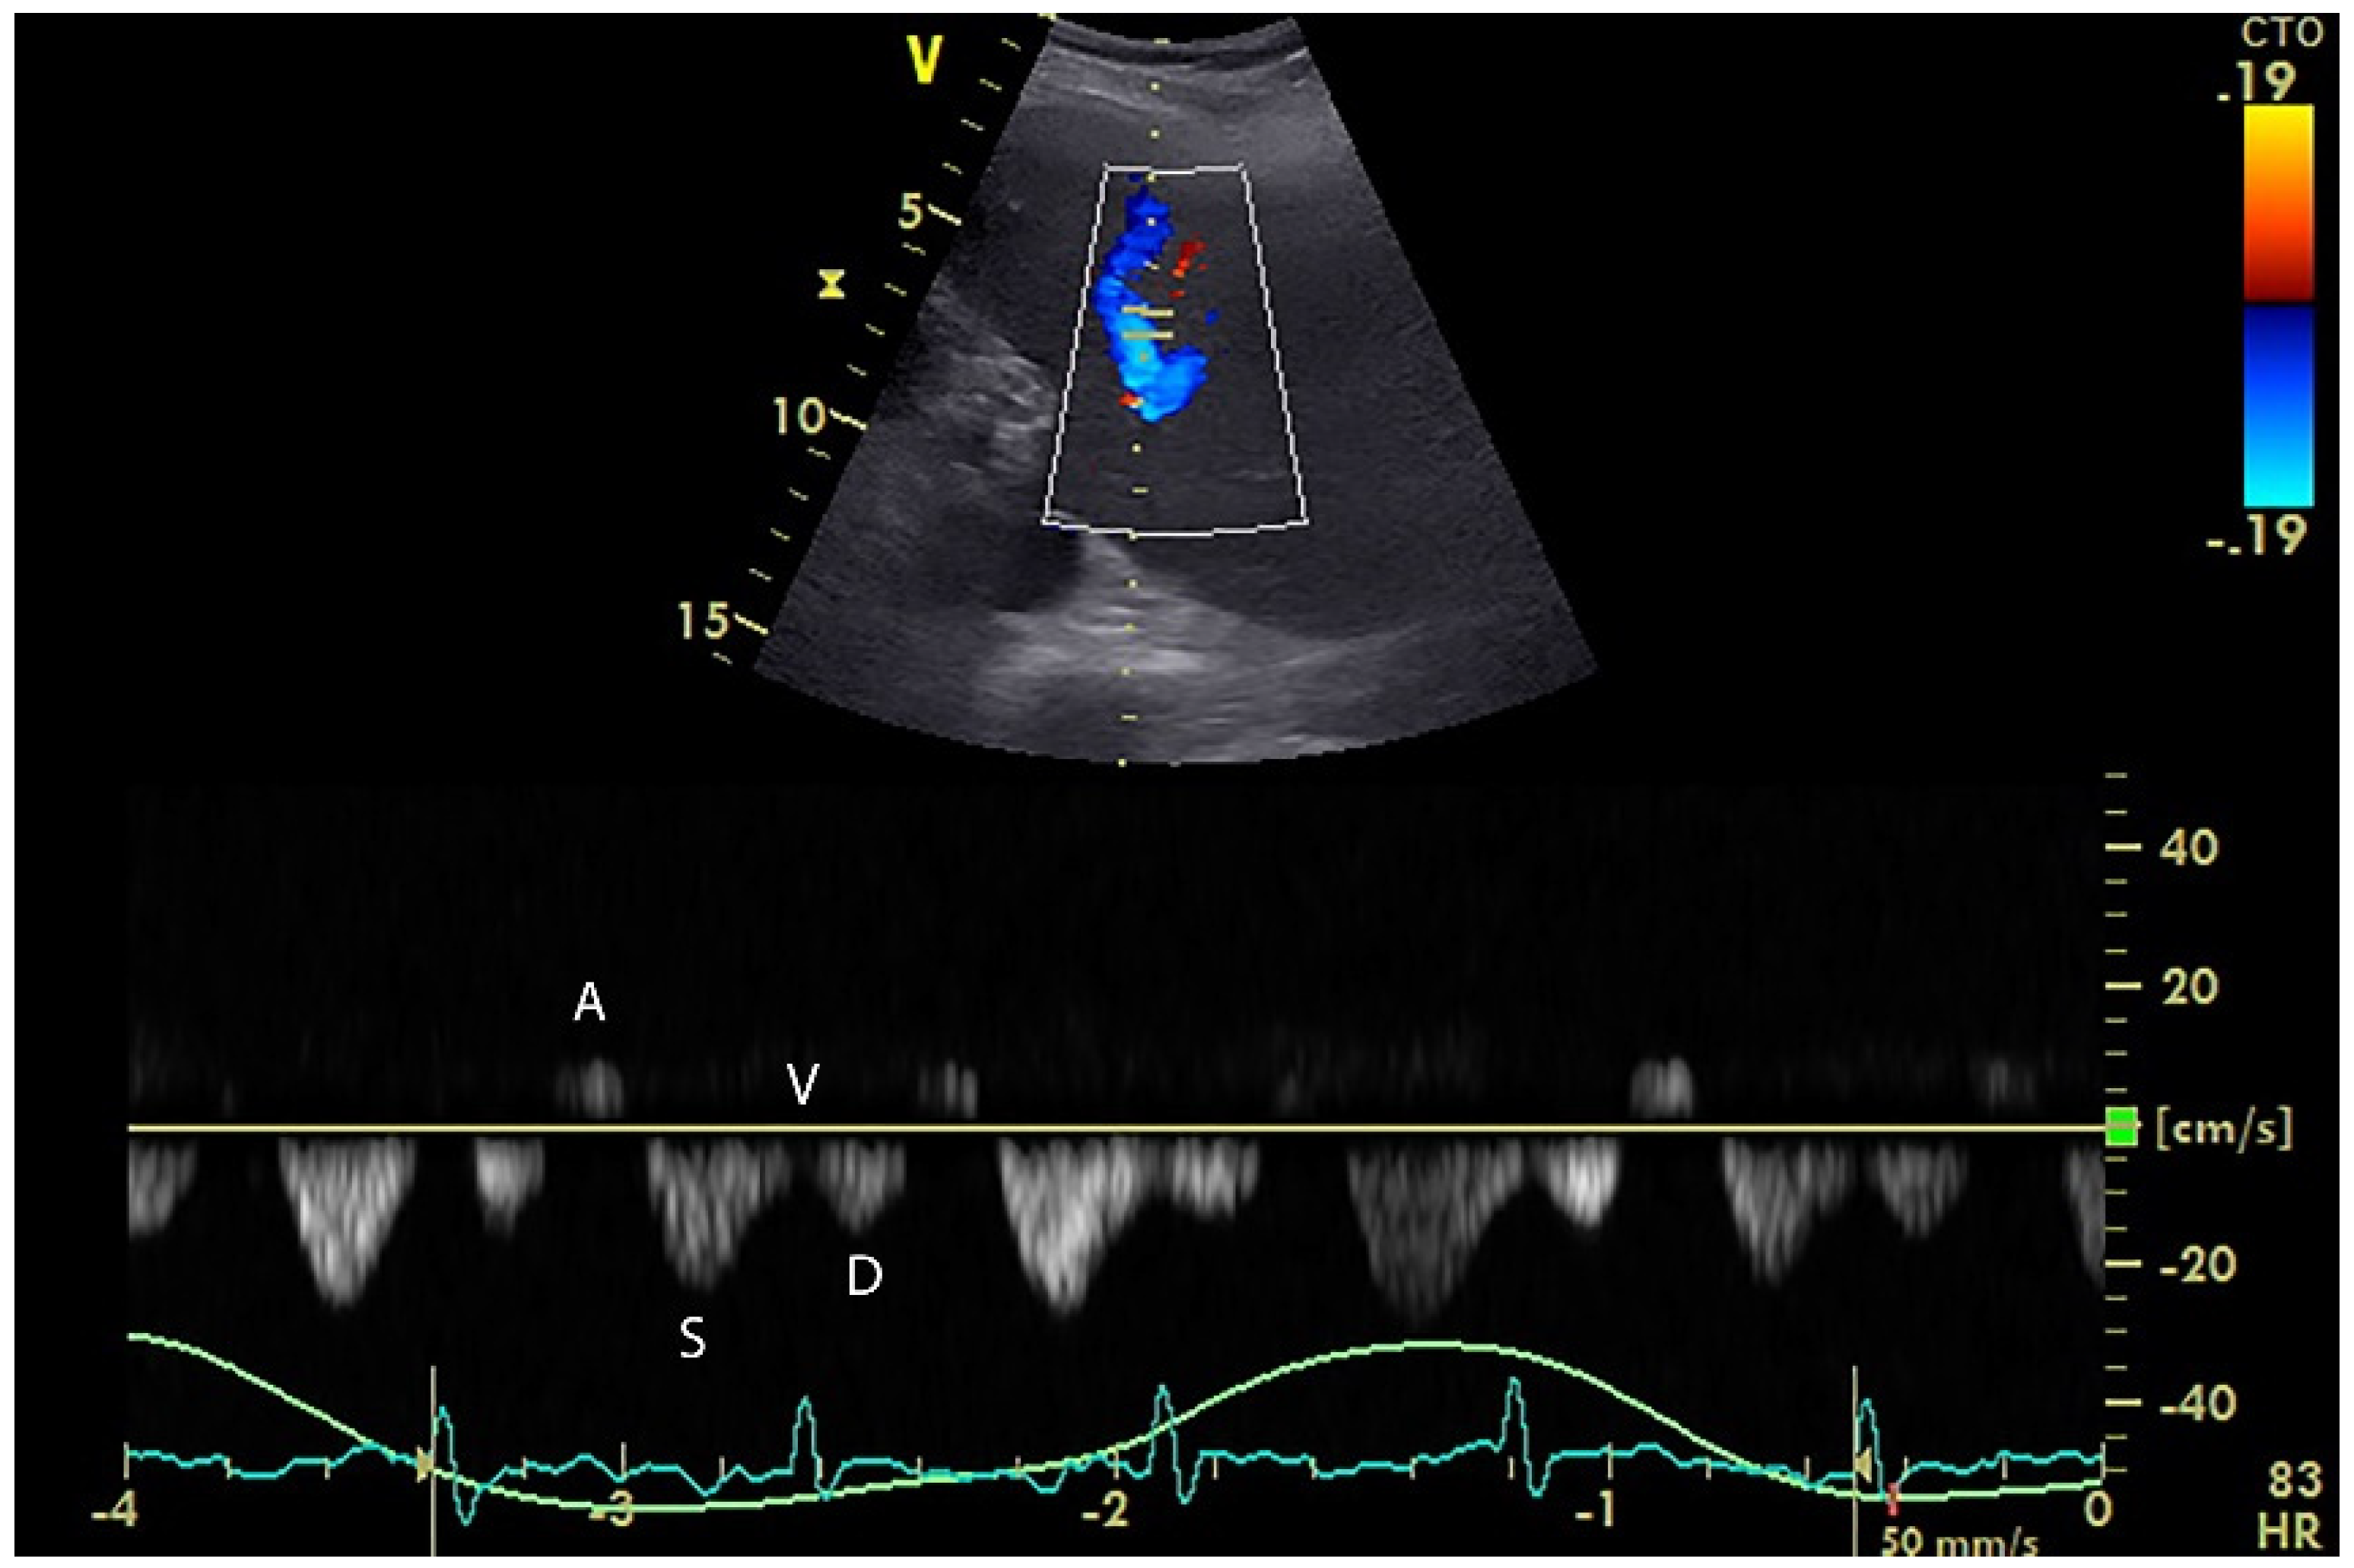

5. Hepatic Venous Flow

- Du, W.; Wang, X.T.; Long, Y.; Liu, D.W. Monitoring Changes in Hepatic Venous Velocities Flow after a Fluid Challenge Can Identify Shock Patients Who Lack Fluid Responsiveness. Chin. Med. J. 2017, 130, 1202–1210. [Google Scholar] [CrossRef]

- Scheinfeld, M.H.; Bilali, A.; Koenigsberg, M. Understanding the spectral Doppler waveform of the hepatic veins in health and disease. Radiographics 2009, 29, 2081–2098. [Google Scholar] [CrossRef] [PubMed]